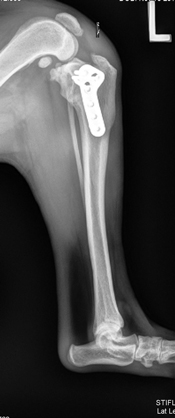

Six weeks after his back surgery, Scruffy was recovered enough to address the rest of his orthopedic problems. Arthroscopy was performed on both of his knees to remove damaged meniscal tissue and evaluate the damage in the CCL’s. Arthroscopy involves looking into a joint with a camera to evaluate the interior surfaces. It is less invasive than traditional ways of looking into a joint, and recovery time is shorter. A tibial plateau leveling osteotomy (TPLO) was performed on the left side, due to the steep tibial slope (33°). A TPLO diminishes the slope angle and stabilizes the knee. The right tibial plateau had a flatter tibial plateau slope due to the way the tibia healed from the previous break.